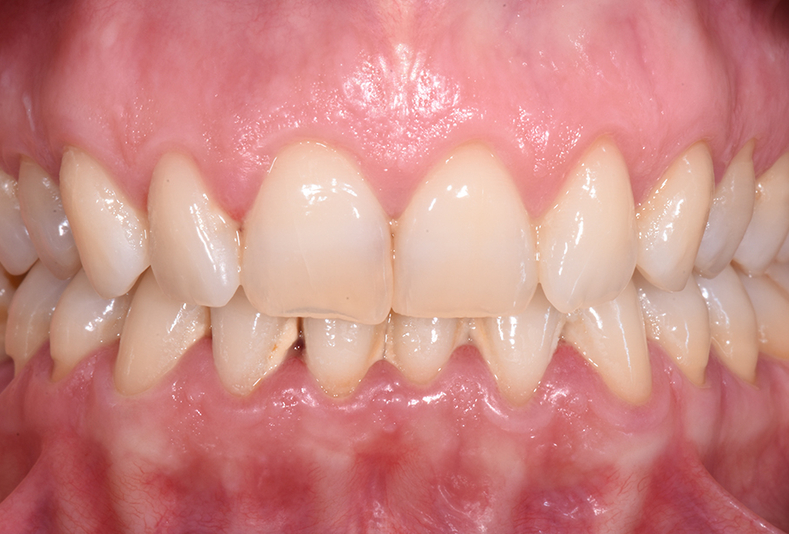

Infiltrazione resinosica per il trattamento non invasivo delle lesioni ipocalcifiche